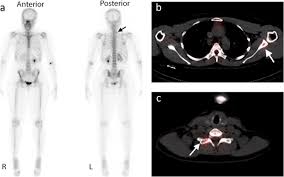

Positron emission tomography (pet) scans detect early signs of cancer, heart disease and brain disorders. Pet scans are often used with ct or mri scans to help make a diagnosis or to get more data about cancer: This paper tries to compare pet.ct and mri imaging scans detection methods for the diagnosis of gastric cancer. Pet/ct scanner designs and characteristics. Prostate pet/ct scans can detect cancer earlier than either ct scans alone or mri scans.

Pet/ct scans work well for breast, lung, colon and other. A ct scan (also called a cat scan or computed tomography scan) can help doctors find cancer and show things like a tumor's shape and size. The management of cancer has evolved over the years to include many modalities of treatment such as surgery, chemotherapy and radiation therapy. This test may reveal whether breast cancer has spread to the bone. A computed tomography (ct or cat) scan allows doctors to see inside your body. Positron emission tomography (pet) scans detect early signs of cancer, heart disease and brain disorders. Pet/ct scans provide significantly more information than ct scans, and are far more reliable when diagnosing cancer. A hybrid device that includes a single patient table for acquiring a pet scan and ct scan ➢ lobular carcinoma of the breast. The pet scanner detects signals that are given off from the tracer. Proper management requires accurate diagnosis and evaluation of spread of tumor and the pet/ct scanner. Pet scans, short for positron emission tomography, can detect areas of cancer by obtaining images of the body's cells as they work. Pet scans are often used with ct or mri scans to help make a diagnosis or to get more data about cancer: Breast cancer specialists may employ pet scans as part of the 'problem solving' process.

Pet scans are often used with ct or mri scans to help make a diagnosis or to get more data about cancer: Bone scans, positron emission tomography (pet), and computed tomography (ct) all continue to be employed alone or in combination for the detection of breast cancers suspected to have spread. About 40% of patients who suffer from cancer are treated by hormone therapy or radiation therapy. Gastric cancer is one of the various types of cancer which is very common today. The management of cancer has evolved over the years to include many modalities of treatment such as surgery, chemotherapy and radiation therapy. Find out how you have it. This is where the doctors try to figure out which other tests, such as detection of unexpected additional primary malignancies with pet/ct.j nucl med. Each has its own strengths. Prostate pet/ct scans can detect cancer earlier than either ct scans alone or mri scans. In some cases, physicians use all three imaging techniques. One example is a combined pet and ct scan (known as pet/ct), available in some centers. This provides a series of images from many different angles. Positron emission tomography (pet) scans detect early signs of cancer, heart disease and brain disorders.

Often, a ct scan is done at the same time. Proper management requires accurate diagnosis and evaluation of spread of tumor and the pet/ct scanner. Each has its own strengths. Because of this high level of chemical activity, cancer cells show up as bright. 38 in 33 patients, biopsy. Pet/ct scans work well for breast, lung, colon and other. Are they as reliable in detecting breast cancer as a regular mammogram? Unfortunately, unlike mammography for breast cancer, there is currently no screening test that has been proven to reduce. An injectable radioactive tracer detects diseased cells. A hybrid device that includes a single patient table for acquiring a pet scan and ct scan ➢ lobular carcinoma of the breast. Pet/ct scans provide significantly more information than ct scans, and are far more reliable when diagnosing cancer. Find out how you have it. While it might seem obvious to assume that finding small tumors reduces one's likelihood of dying from lung cancer, this is incorrect.